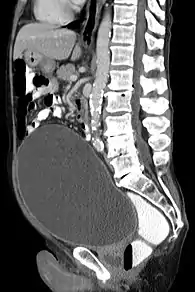

Rétention urinaire aiguë avec vessie très dilatée. | |